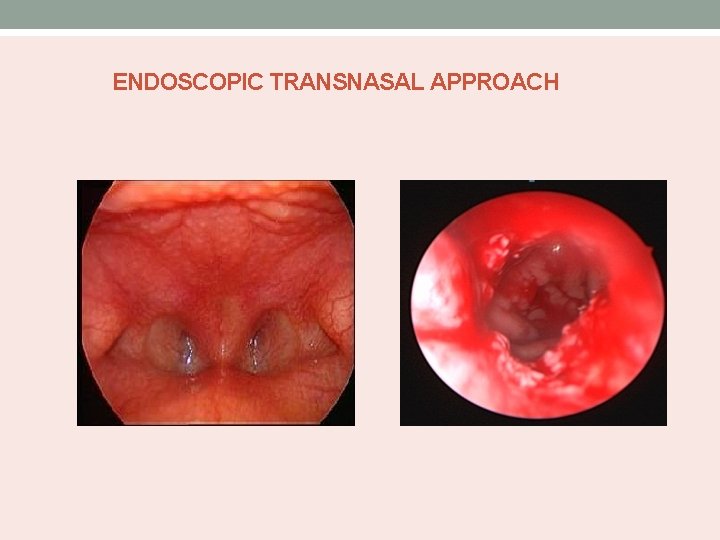

ENDOSCOPIC TRANSNASAL APPROACH

TRANSPALATAL APPROACH • An incision is made around summit of the alveolar ridge or at the gingivopalatal margin if teeth are present. • The mucous membrane of hard palate is elevated, using Cottle septal elevator. • Flap is developed posteriorly, until edge of hard palate is reached.

• The nasopharynx is entered. • Using cutting burs of suitable size, the posterior end of the hard palate removed to expose the bony atresia. • Continuity of the nasal cavity restored by drilling away the obstructing bone, the posterior end of the vomer being removed at the same time. • Bilateral nasal stent placed.